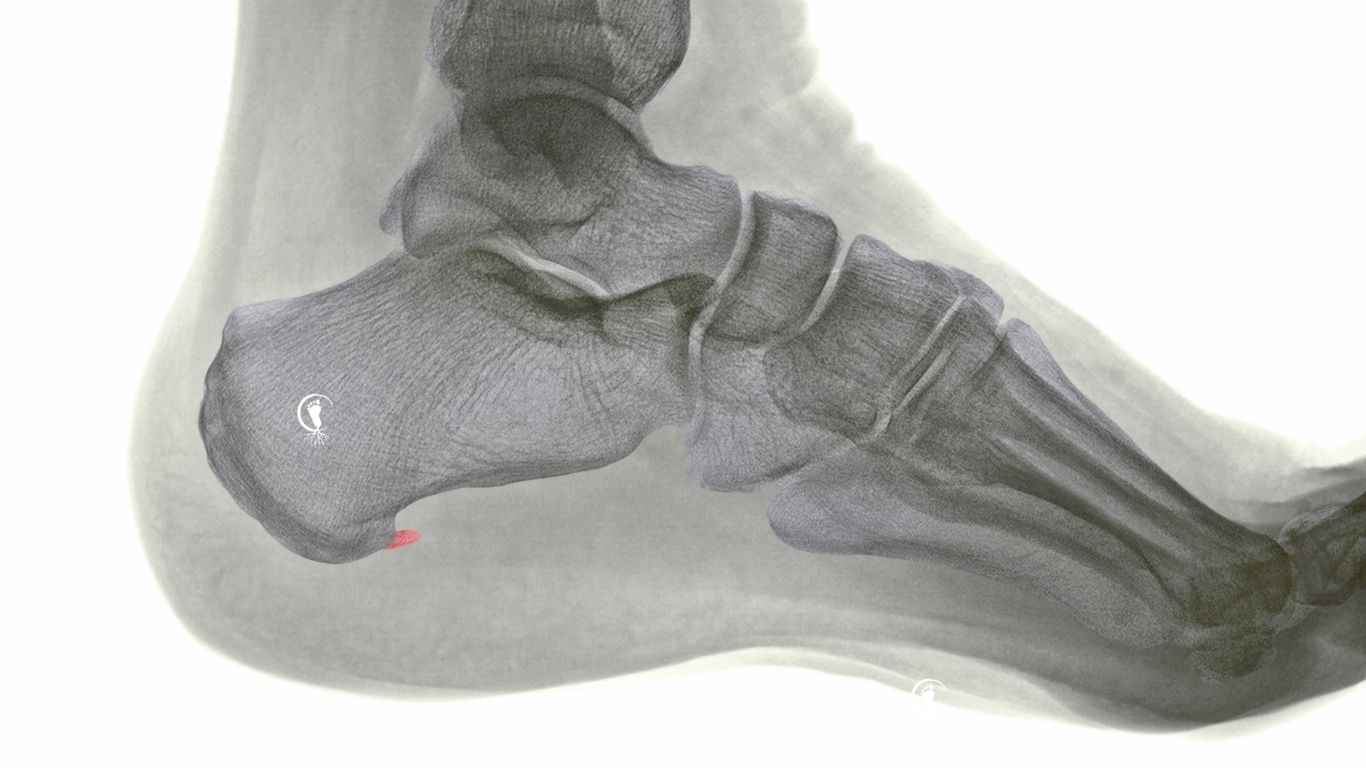

Al Centre Cospedia de Badalona, abordem l’esperó calcani a Badalona des d’una mirada global i personalitzada. L’esperó calcani és una calcificació que apareix a l’os del taló com a resposta a tensions repetides en el temps, especialment de la fàscia plantar.

Tot i això, no sempre és l’esperó el que provoca el dolor. Moltes persones tenen un esperó calcani sense molèsties, mentre que d’altres presenten dolor sense que hi hagi cap calcificació visible.

Per això és important no quedar-se només amb la imatge radiològica, sinó entendre què està passant a nivell funcional.